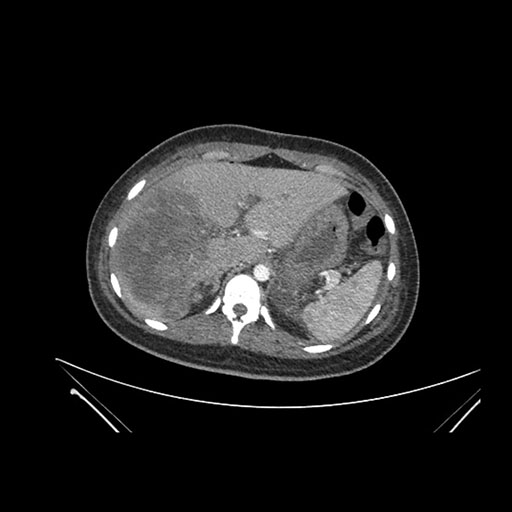

Axial Arterial

Axial Venous